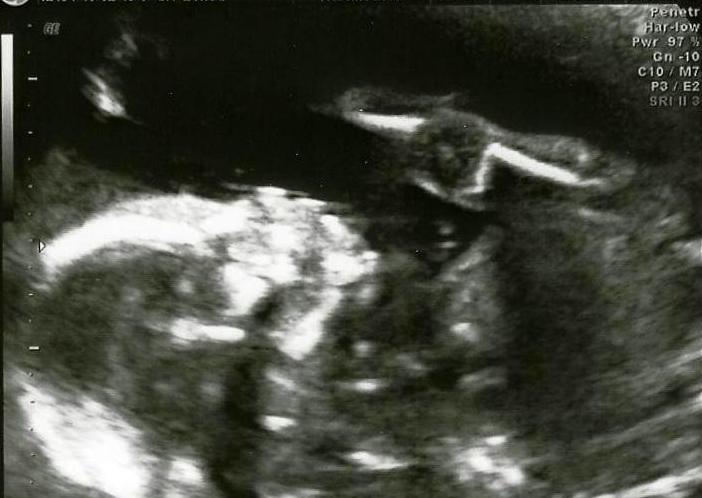

Tiraram-me as medidas no hospital.

PS - Vou começar a tirar Medicina porque tenho de curar um rim que tenho dilatado. Se chumbar volto a tentar daqui a 20 anos e deixo a minha "cura" para os profissionais quando eu nascer.

Quando eu nascer??? O que é nascer se eu já cá estou e sinto? Tenho de perguntar aos meus pais, ou não, que já levei uma "rebocada" da minha logo de manhã para eu não ser preguiçoso. Ela diz que tenho de "curar" o rim porque agora é melhor e mais saudável, ralhou comigo mas explicou-me tudo e fez-me festas de incentivo. Será que consigo tirar boas notas?